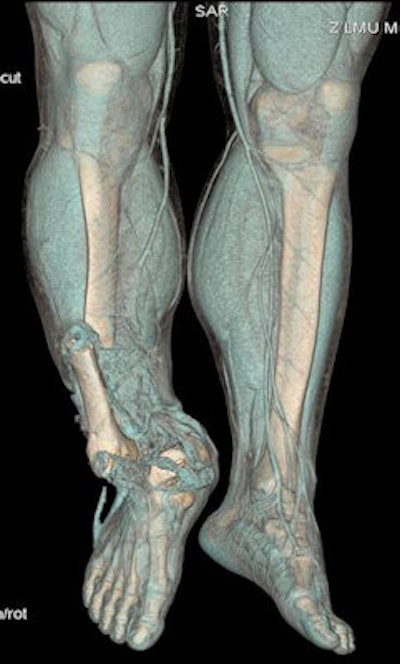

CT volumetric representation of a complex amputation injury of the right lower extremity due to trauma sustained from road traffic accident. Image courtesy of Dr. Stefan Wirth.